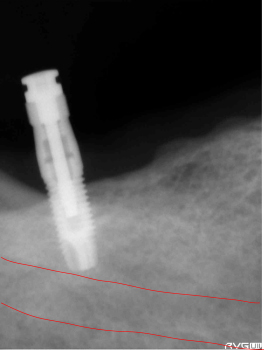

横に2本目のインプラントを植立していきます。 直径1.5mmのドリルで穴を掘りますが、1本目のインプラントに近接しているのがわかります。 従ってスライド掘削方法で穴の直径を大きくします。 |

最初に1.5mmのドリルで試し掘りした時の距離を変えずに2本目のインプラント終了。 骨に深さがなかったので、下歯槽管の真上まで植立。ドリルが1回転(360度)で1mm進むので、ドリルを180度回せば0.5mm、90度で0.25mmの精度で合わせる事が出来ます。